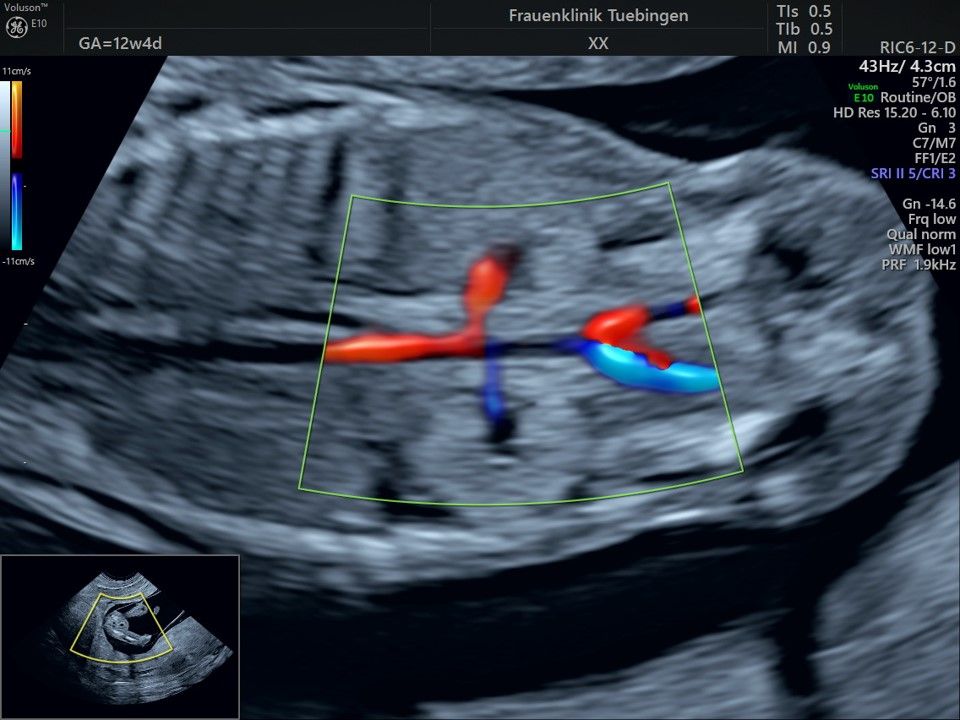

Mithilfe des Ersttrimester-Screenings kann das persönliche Risiko einer Präeklampsie bestimmt werden. Dazu wird die Vorgeschichte der Schwangeren, der aktuelle Blutdruck, das Ergebnis der Ultraschalluntersuchung (Widerstand in den Gebärmutter-nahen Gefäßen) und der Blutabnahme bei Ihnen (PAPP-A) kombiniert. Sollte das Risiko über 1:100 sein, empfehlen wir die tägliche Einnahme von Aspirin 150mg bis zu 35.SSW und eine gezielte Überwachung der weiteren Schwangerschaft.

Das Ergebnis der Ultraschalluntersuchung ist wegweisend. Dabei wird der Fet vermessen, die Organe werden untersucht und die sonographischen Marker zur Risikoberechnung für Chromosomenstörungen werden beurteilt. Das sind: die Nackentransparenzdicke, Nasenbein sowie der Blutfluss in der rechten Herzhälfte und im Ductus venosus, einem Gefäß in der Leber des Feten.